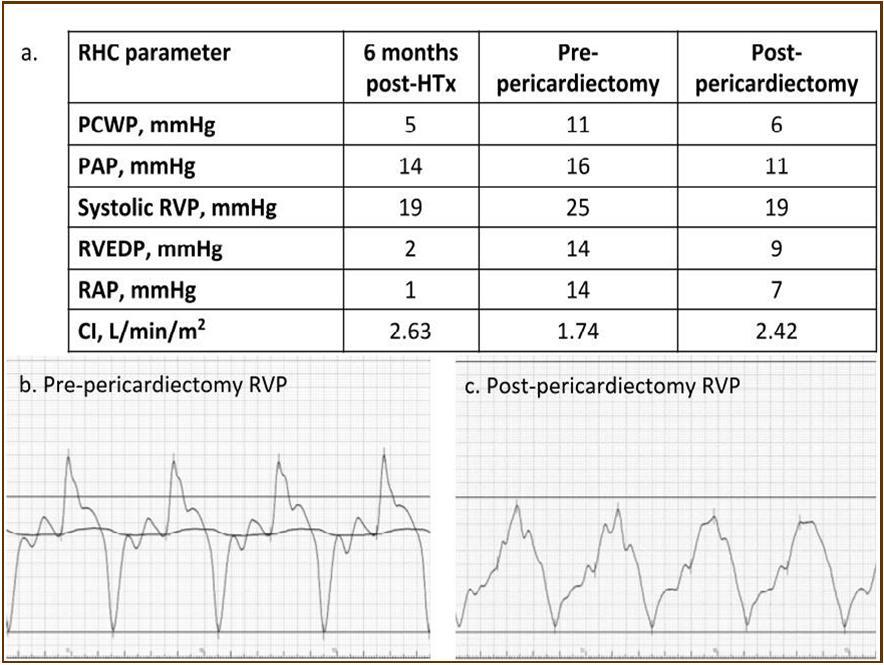

At the age of 52 years, the patient was admitted to our institution for both evaluation of heart failure and regular right heart catheterization including EMB. With respect to allograft rejection, ACR was again detected on regular EMB, and the immunosuppressive regimens were strengthened. Further echocardiographic investigations were conducted to explore the implications of findings indicative of constrictive physiology with thickened pericardium. Respiratory variation in both mitral and tricuspid inflow velocities was seen, but these findings did not meet the complete criteria for CP diagnosis (Figure 1c-e). Magnetic resonance imaging of the heart revealed seroma and a thick cystic-like capsule tightly adhered to the right ventricle (Figure 2a, b). Right heart catheterization revealed elevation of right atrial pressure with severely reduced cardiac index (Figure 3a). The classic dip-and-plateau pattern of right ventricular diastolic pressure and equalization of right atrial pressure and right ventricular diastolic pressure were also observed (Figure 3b). Based on these results, effusive CP or cardiac tamponade-like hemodynamics were strongly suspected, although the etiology remained unknown. Therefore, at 3 years post-HTx, the patient initially underwent removal of the seroma through exploratory lateral thoracotomy to elucidate the etiology of the disease. Yellowish fluid was found and the fluid was completely aspirated. Immunosuppressive regimens including everolimus, which may interfere wound healing, were temporarily converted to standard three-drug regimens. Removal of the seroma via lateral thoracotomy did not lead to improvement in symptoms or hemodynamics. Pathological analysis revealed fibrin and seroma, but no malignant cells or infection. Since the initial procedure did not have any effect on the patient’s symptom, pericardiectomy through median sternotomy was performed at two months after the initial procedure. Intraoperative findings indicated a thickened pericardium and effusion in front of the right ventricle. At first, after sternotomy and adhesiotomy, the tissue in front of the right ventricle, which appeared to be thickened parietal pericardium, was completely resected and the effusion fluid was removed. However, high central venous pressure (20 mmHg) persisted, resulting in a displacement of the left ventricle by the right ventricle. Therefore, additional tissue from the front of the right ventricle was excised, corresponding to diffusely thickened visceral pericardium and epicardium. After the procedure, central venous pressure decreased from 20 to 10 mmHg, and displacement of left ventricle resolved. Pathological analysis of the resected tissues demonstrated chronic fibrosis and chronic inflammation with plasma cells, but no infectious etiology was identified (Figure 4 a, b). After the pericardiectomy, hemodynamics (Figure 3a, c) and symptoms improved, and the patient is currently experiencing a favorable clinical course without complications.

Figure 3.Hemodynamic parameters. Both right and left ventricular filling pressure (RAP, and PCWP) were upregulated and CI was reduced just before pericardiactomy. RAP, and PCWP were lowered, and CI was upregulated after pericardiectomy. The classic dip-and-plateau pattern of right ventricular diastolic pressure was observed (b). CI, cardiac index; HTx, heart transplantation; PAP, pulmonary artery pressure; PCWP, pulmonary capillary wedge pressure; RAP, right atrial pressure; RHC, right heart catheterization; RVEDP, eight ventricular end-diastolic pressure; RVP, right ventricular pressure.